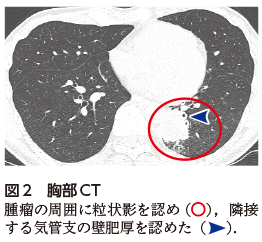

• A2:肺化膿症のほか,原発性肺がんなどの疾患を疑い,胸部CT検査および気管支鏡検査の再検を行う(図2図3).

胸部単純X線写真では一見すると両肺野に明らかな異常陰影を指摘できないが,注意深く観察すると下行大動脈左縁の陰影が途切れていることがわかる(図1).このような所見をシルエットサインが陽性であると表現し,病変が下行大動脈と接していることを示している.このような心陰影と重なった結節影や腫瘤影を見つける際に,下行大動脈とのシルエットサインの有無はきわめて有用な所見である.胸部CTではS6からS10にかけて腫瘤を認め周囲に粒状影を伴っており(図2),また腫瘤に隣接する気管支の壁肥厚もみられる(図2).これらの画像所見から肺化膿症を含めた感染症が第一に疑われたものの,原発性肺がんを含めた他疾患との鑑別目的に気管支鏡検査を施行した.経気管支肺生検(transbronchial lung biopsy:TBLB)を行い,一般細菌および抗酸菌培養検査は陰性であったものの,組織診では膿瘍や炎症細胞浸潤のほかにグラム染色およびグロコット染色陽性となる桿菌を多数認め,肺放線菌症が疑われた(図3).本症例では経口ペニシリン系抗菌薬による内服治療を開始し,治療開始後約4カ月時点で胸部単純X線写真上の腫瘤影はほぼ消退した(図4).今後は計6~12カ月を目安に抗菌薬加療を継続する方針としている.

図2